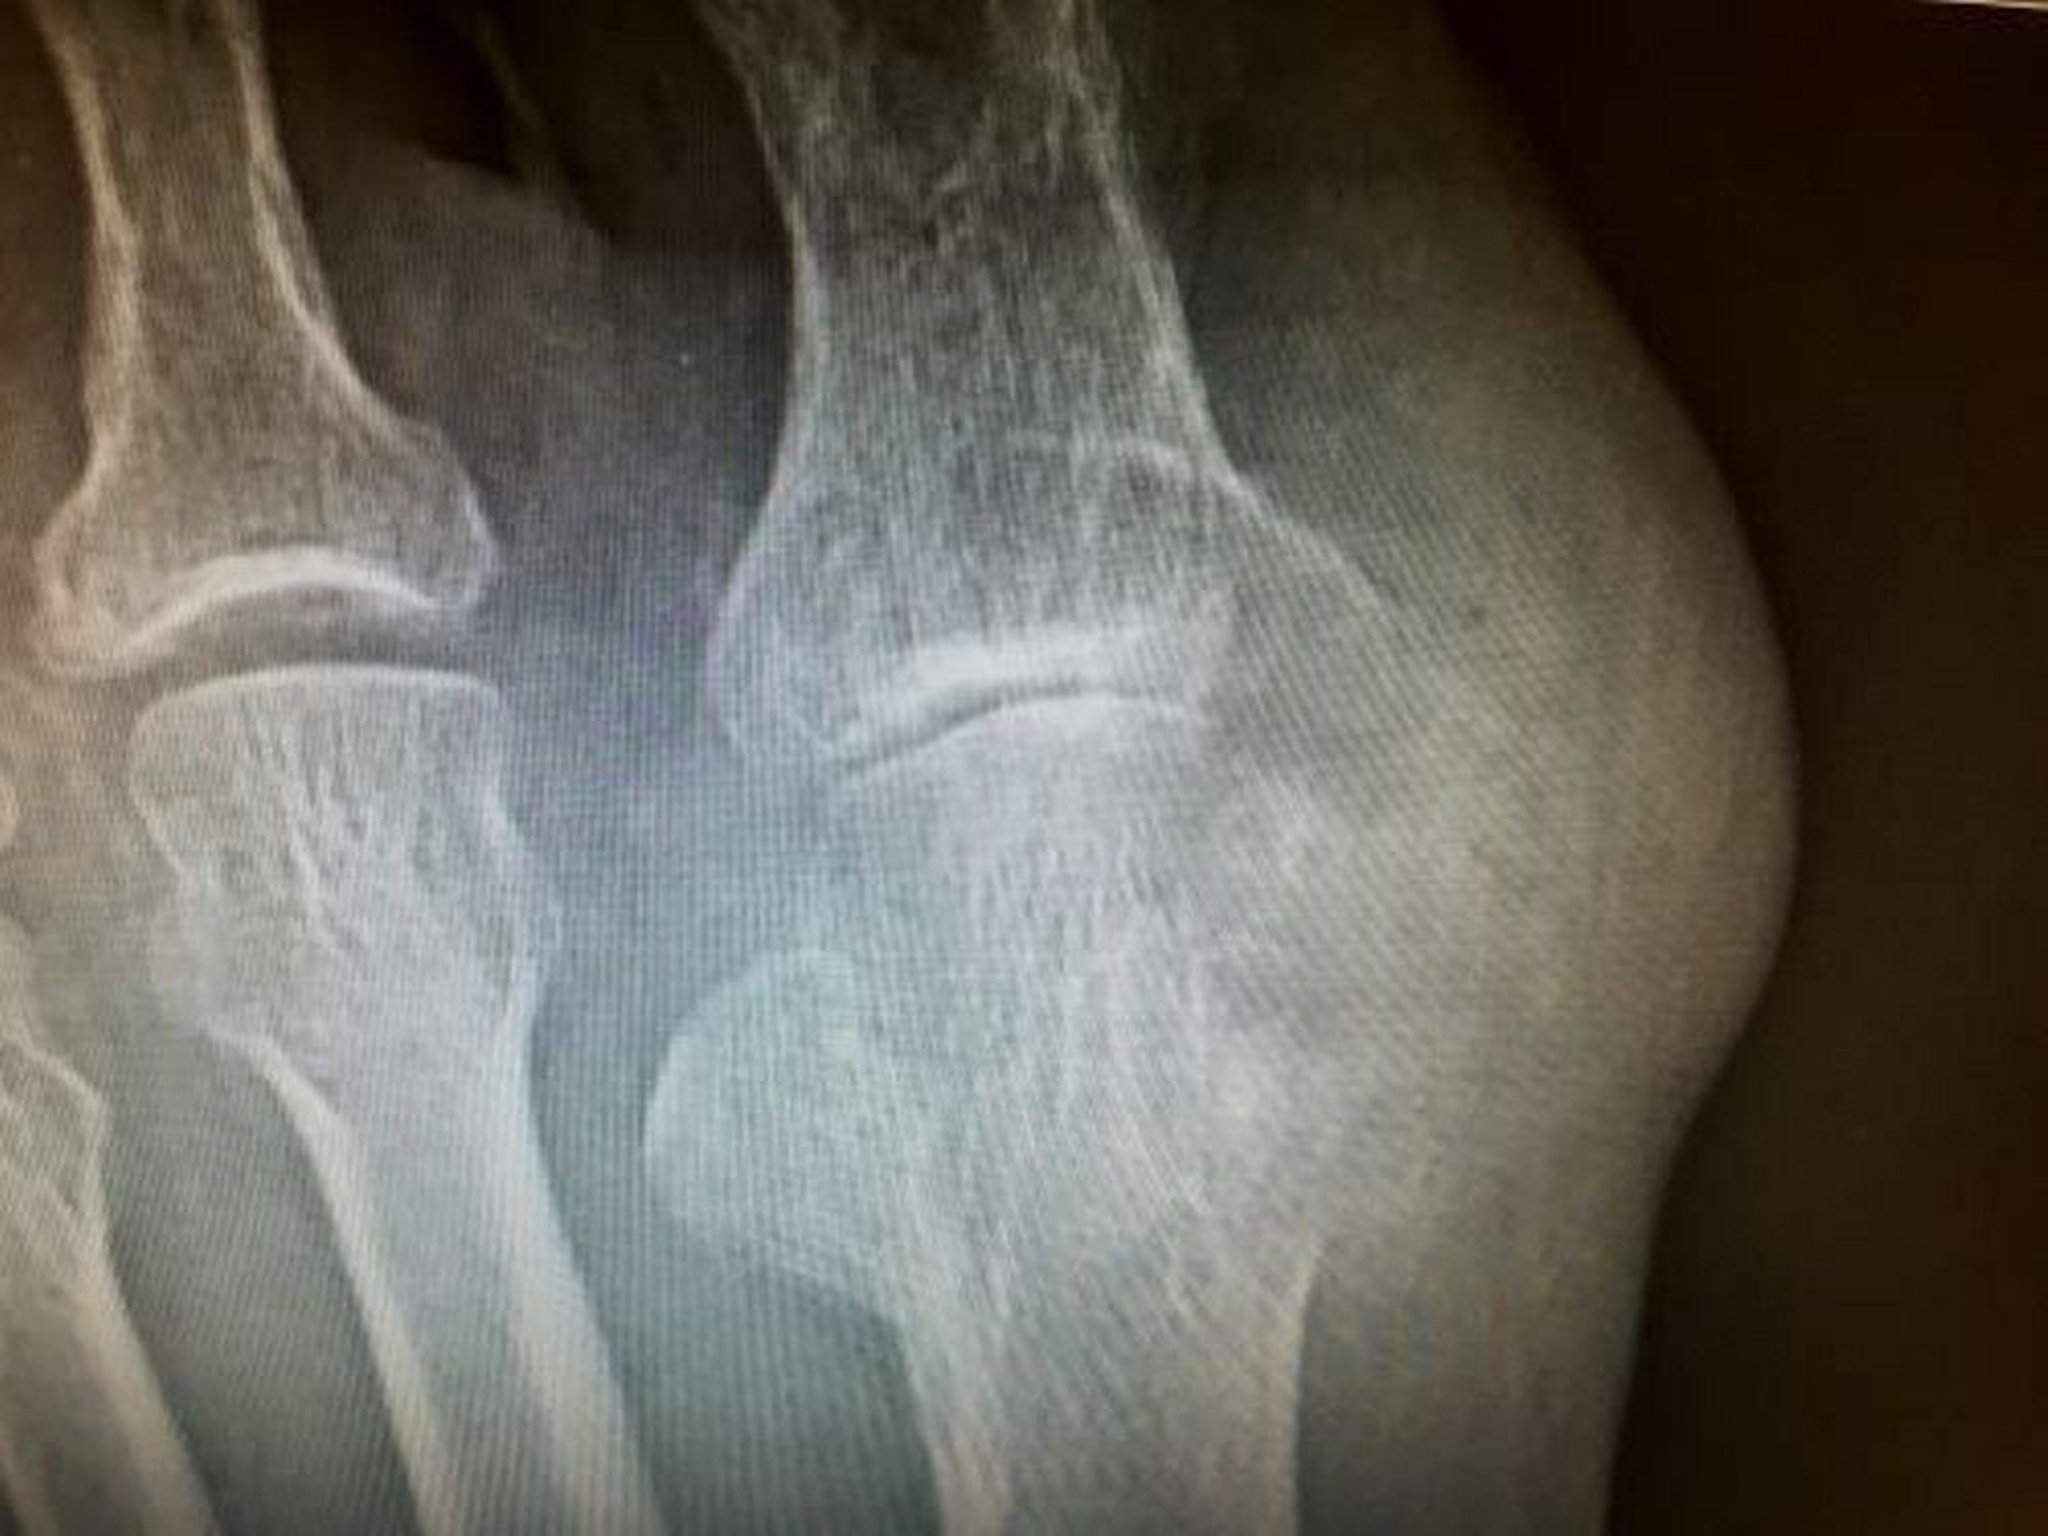

Tophus with Erosion

This photo shows large erosions caused by tophi involving the distal metatarsal and proximal phalanx of the great toe.

Image courtesy of N. Lawrence Edwards, MD.